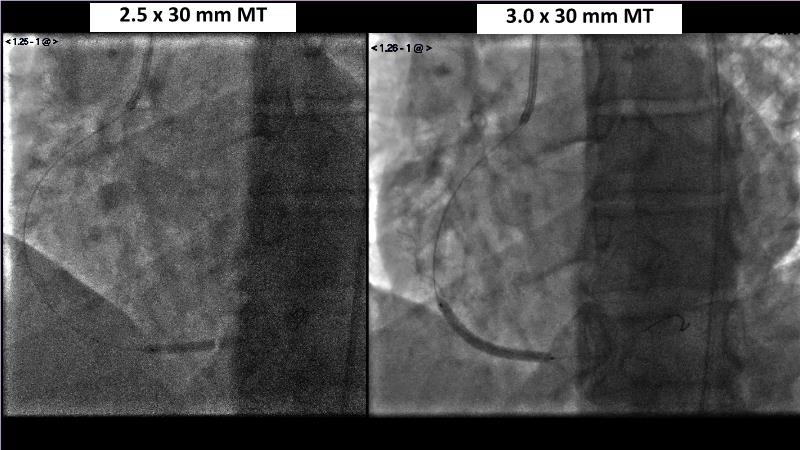

Browse this EuroPCR 2024 session to explore the safety and efficacy of sirolimus-coated balloons from pre-clinical data, review MagicTouch data from real-world populations with case-based examples, and learn about the MagicTouch sirolimus-coated balloon clinical programs. Discover insights and takeaways from the significance of the EASTBOURNE subgroups, and analyze the challenges and opportunities in PCI for diabetic patients.

- To learn from the real world registries and complex cases to understand the practical implications and potential of the device in diverse patient population